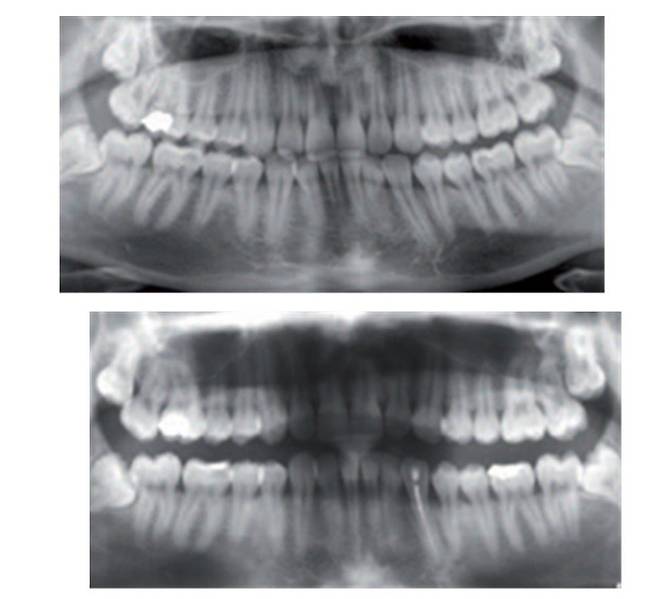

협회에 따르면 실제로 구입한 셀프 치아 장치로 인해 치아나 잇몸 손상, 부정 교합, 턱관절 장애 유발, 파손 또는 파절로 인한 기도 흡입 등 다양한 부작용 유발 사례들을 쉽게 찾아볼 수 있다.

국내 유명 쇼핑몰 후기에서도 이갈이 방지를 위해 셀프 마우스피스를 구매했던 소비자들이 ‘치은 부종’ 등 여러 부작용을 겪고 있는 사례가 확인됐다. 셀프 이갈이 방지 장치를 구매해 2주간 사용했다는 A씨는 “양치는 물론 음식 먹기도 고통스럽다”는 후기를 남겼다. 협회는 “사진 상 구강 내에 점막 궤양이 유발된 것으로 보인다”고 밝혔다.